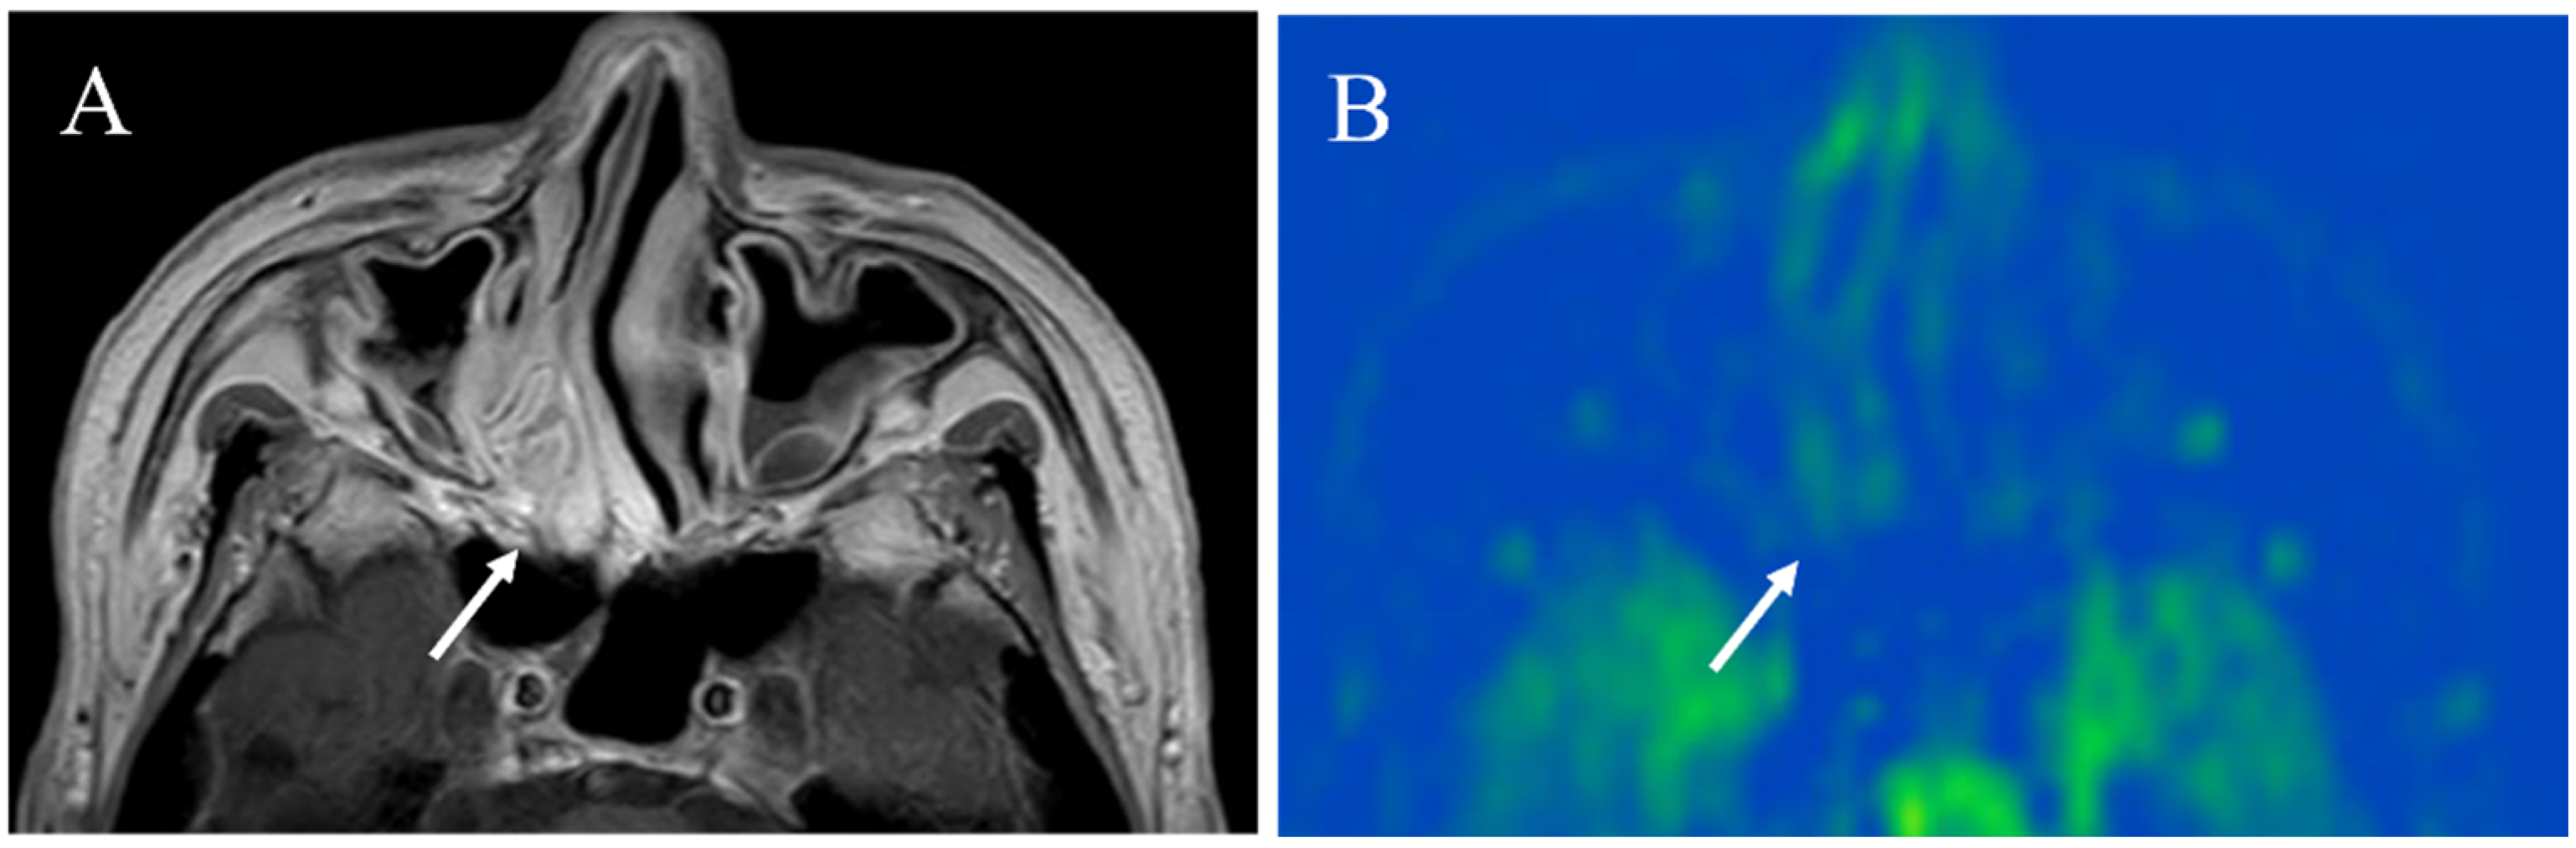

Figure 8. A 23-year-old male with juvenile nasopharyngeal angiofibroma: (A) STIR shows a mass with high signal intensity (arrow) and subtle flow voids within the mass (arrowhead); (B) pCASL image shows markedly elevated blood flow within the lesion (arrow) (mean of 380.42 mL/100 g/min).